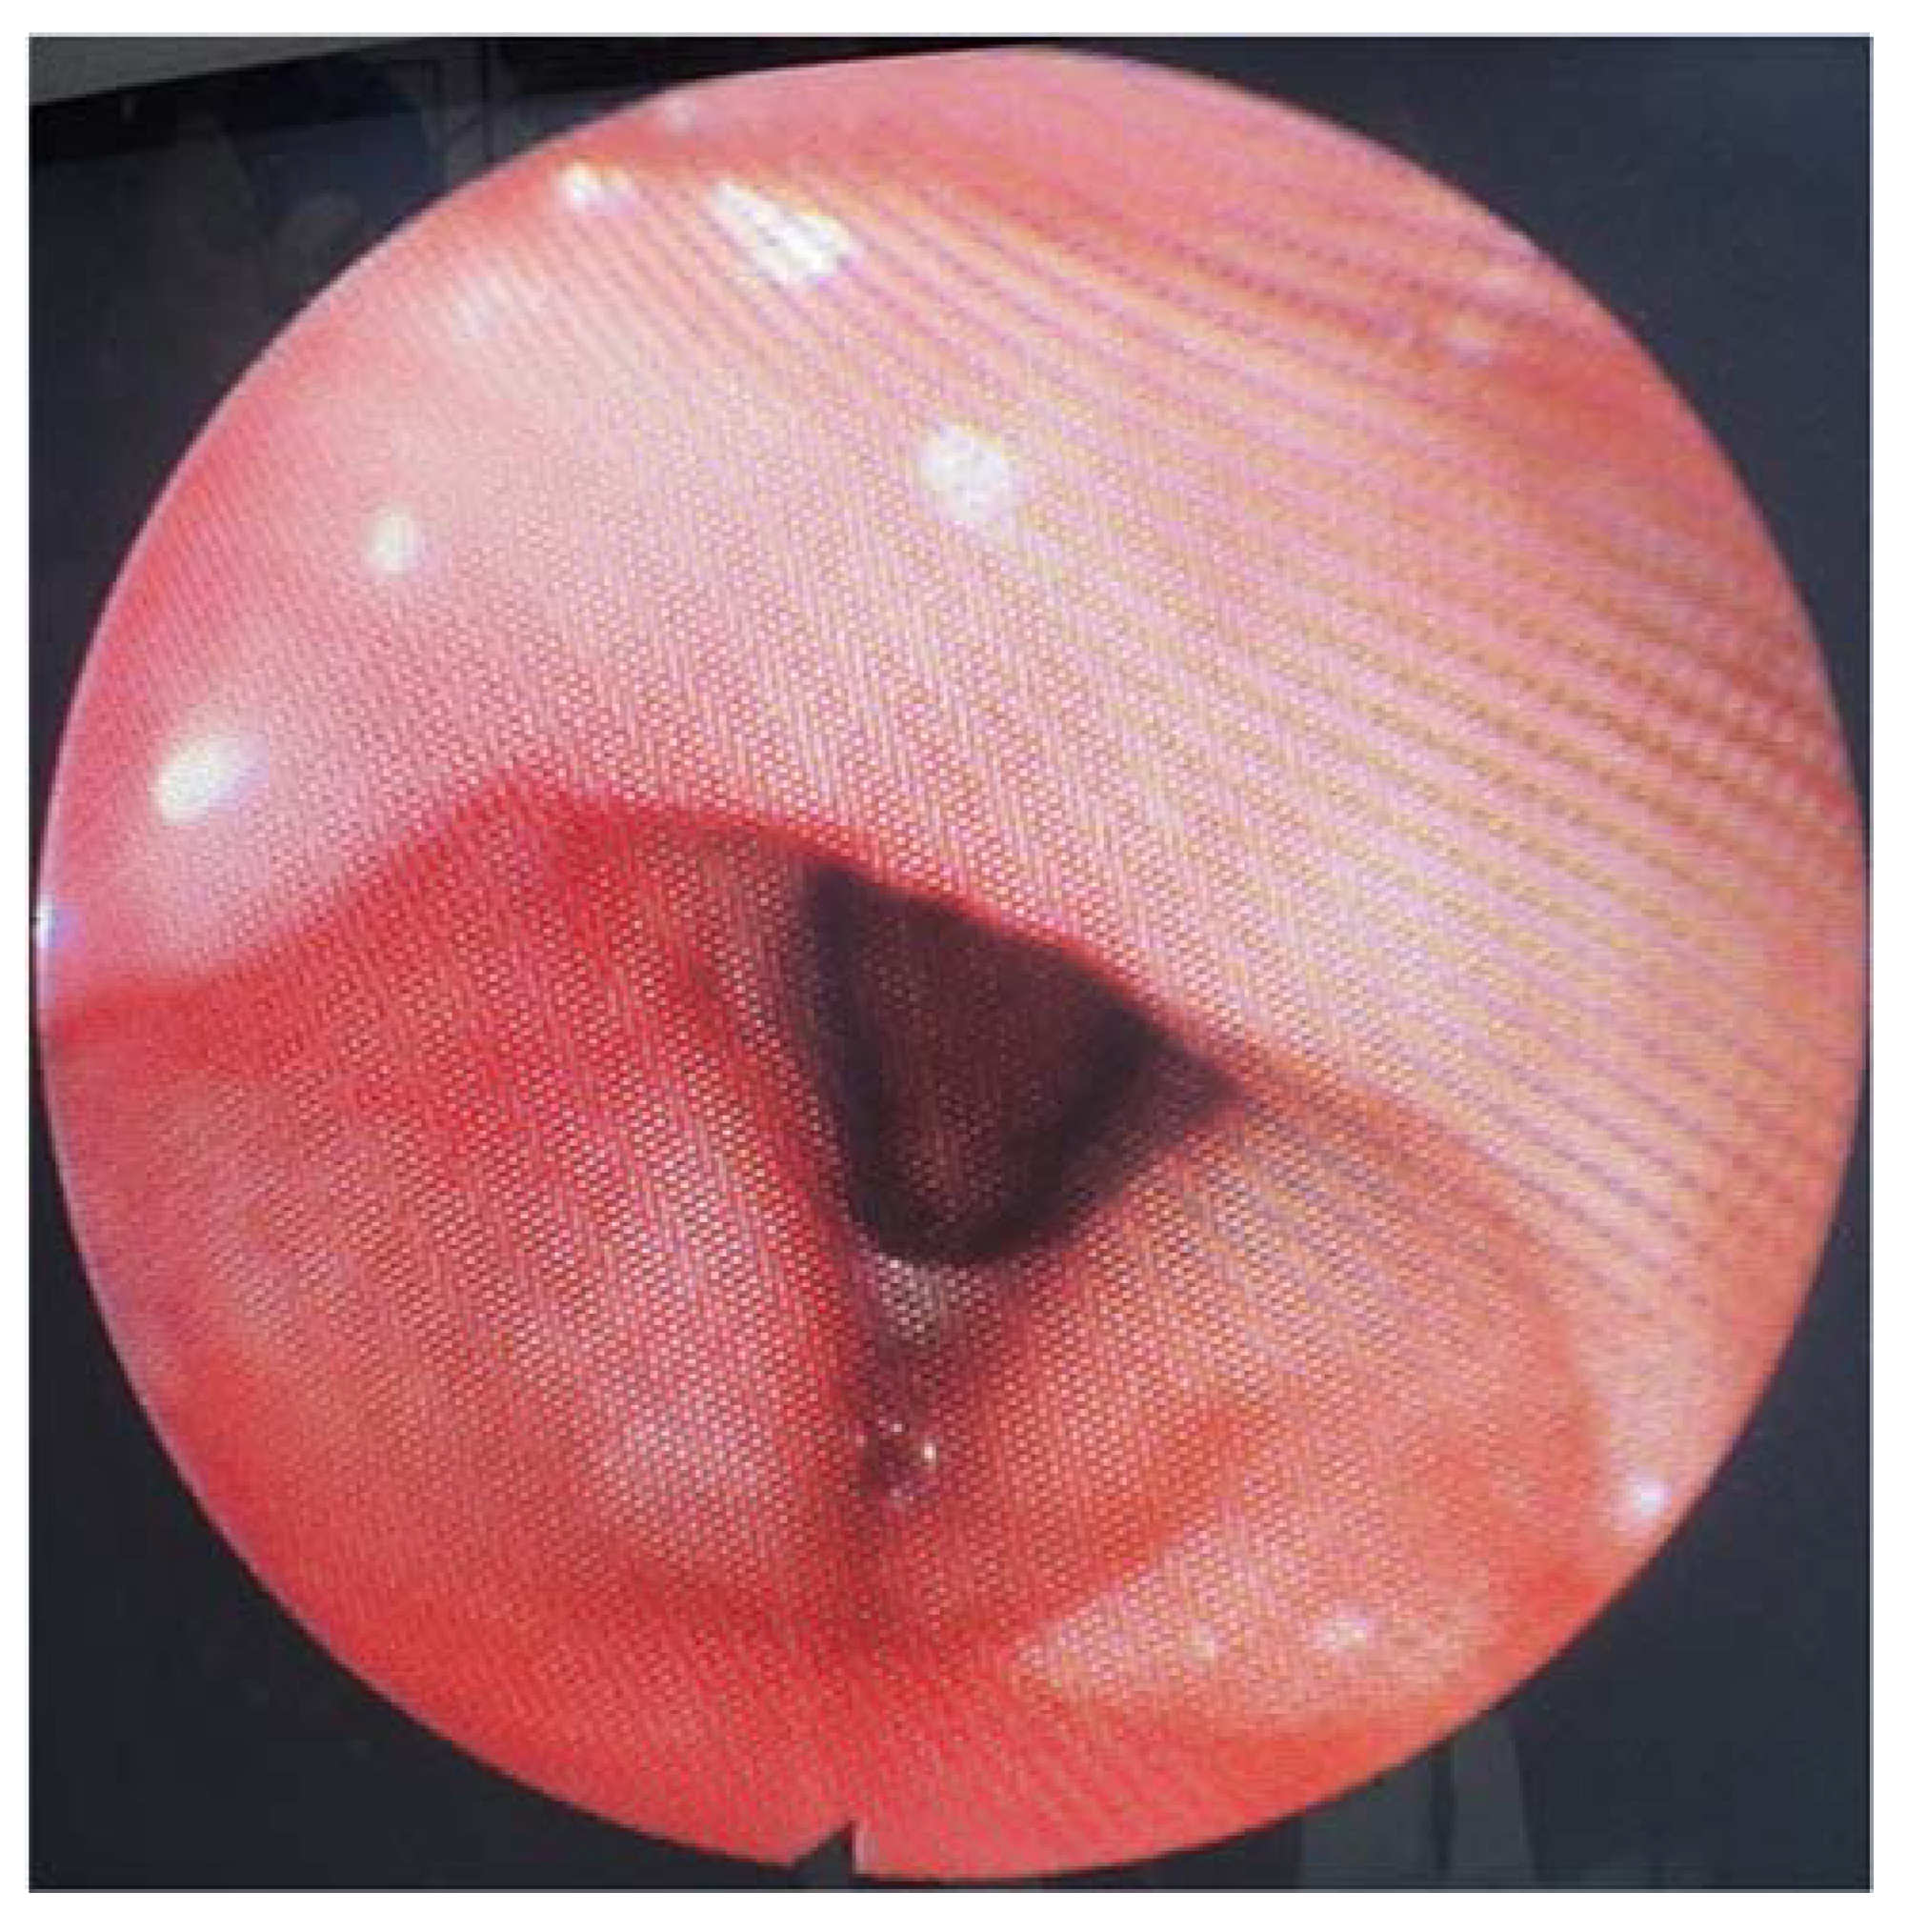

The flexible video laryngoscopy examination revealed a supraglottic mass covering the left aryepiglottic fold and the left arytenoid cartilage, extending to the ipsilateral pyriform sinus. The tumor presented a pronounced vascular draw, having a blueish color. The tumor deviated from the left hemilarynx medially, thus decreasing the movement of the left true vocal fold. The tumor tilted over the laryngeal inlet’s opening, causing breathing difficulties. The right vocal fold has a normal aspect, with normal movement, while the tumor did not obstruct the glottic space (Figure 1).

Figure 1.

The tumor bulges into the laryngeal inlet (the laryngeal inlet is marked by the arrow and the tumor by a star).